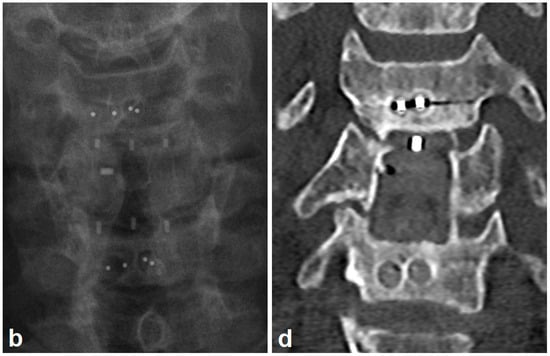

3.2. Radiologic Outcomes